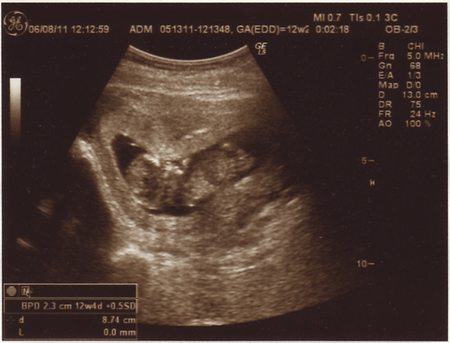

まだまだ推定6週目。

ちっちゃい、マメちゃんの姿と心拍を確認することが出来ました。

黒い丸が、胎嚢で赤ちゃんが入っている袋。その中の白いぽちが胎芽といって赤ちゃんの赤ちゃんです(^^

まめちゃん、現在3ミリとのこと・・・・